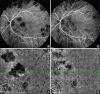

A structurally and functionally intact choroid tissue is vitally important for the retina function. Although central retinal artery is responsible to supply the inner retina, choroidal vein network is responsible for the remaining one-third of the external part. Abnormal choroidal blood flow leads to photoreceptor dysfunction and photoreceptor death in the retina, and the choroid has vital roles in the pathophysiology of many diseases such as central serous chorioretinopathy, age-related macular degeneration, pathologic myopia, Vogt-Koyanagi-Harada disease. Biomarkers of choroidal diseases can be identified in various imaging modalities that visualize the choroid. Indocyanine green angiography enables the visualization of choroid veins under the retinal pigment epithelium and choroidal blood flow. New insights into a precise structural and functional analysis of the choroid have been possible, thanks to recent progress in retinal imaging based on enhanced depth imaging (EDI) and swept-source optical coherence tomography (SS-OCT) technologies. Long-wavelength SS-OCT enables the choroid and the choroid-sclera interface to be imaged at greater depth and to quantify choroidal thickness profiles throughout a volume scan, thus exposing the morphology of intermediate and large choroidal vessels. Finally, OCT angiography allows a dye-free evaluation of the blood flow in the choriocapillaris and in the choroid. We hereby review different imaging findings of choroidal diseases that can be used as biomarkers of activity and response to the treatment.